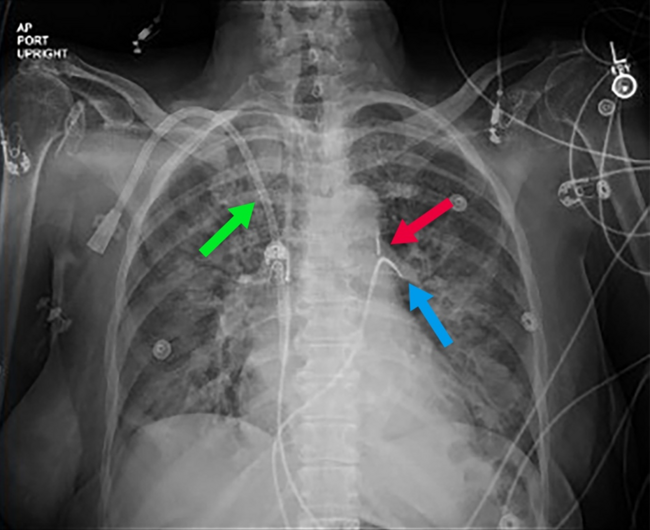

Urgent coronary angiography showed severe 3-vessel disease with 80% to 90% ostial left main and mid-left anterior descending stenosis. The left ventricular end-diastolic pressure was 20 mm Hg. A 40-cc intra-aortic balloon pump (IABP) was placed for hemodynamic support (Figure 1) and percutaneous coronary intervention was performed. Hypotension and vasopressor requirement persisted despite counterpulsation. The indirect Fick cardiac index was 3.6 L/min/m2 with a calculated systemic vascular resistance of 593 dyne-sec-cm-5. Close inspection of the arterial pressure tracing showed an unusually low assisted end-diastolic pressure of 29 mm Hg with substantial improvement when counterpulsation was paused (Figure 2). Echocardiography confirmed normal biventricular systolic function and excluded pericardial effusion and aortic regurgitation. Liver imaging and cortisol level were normal, and a bedside arteriovenous fistula occlusion test did not result in an increase in blood pressure.